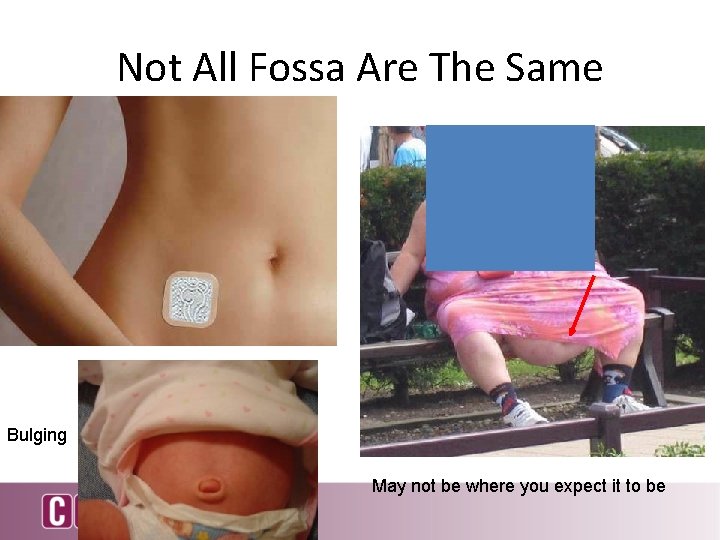

Not All Fossa Are The Same Bulging May not be where you expect it to be